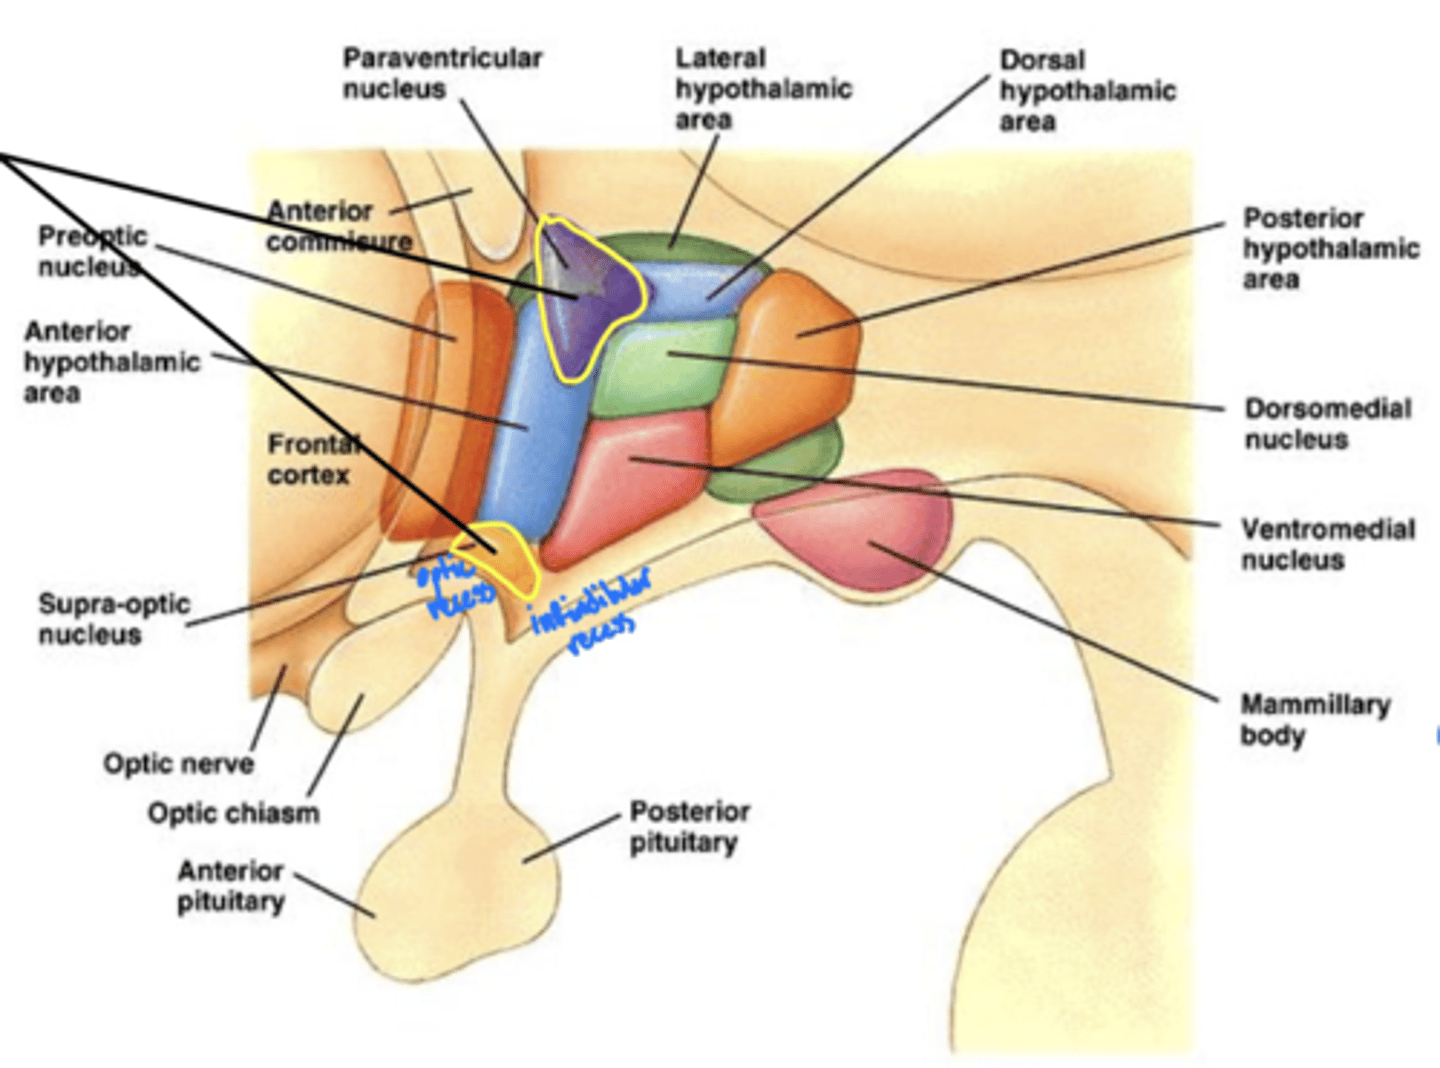

What is the function of the hypothalamus?

homeostasis

What is the hypothalamus just superior to?

1. optic chiasm

2. pituitary gland

What nuclei of the hypothalamus produce hormones for the pituitary gland?

1. paraventricular nucleus

2. supra-optic nucleus

Where is the hypothalamus in relation to the thalamus?

anteroinferior (in front and below)

Where is the epithalamus in relation to the thalamus?

posterosuperior (behind and above)